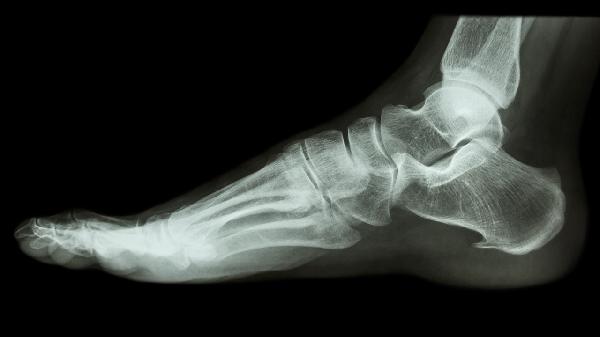

左足跟骨粉碎性骨折怎么恢复

左足跟骨粉碎性骨折可通过石膏固定、药物镇痛、康复训练、手术复位、物理治疗等方式恢复。骨折通常由高处坠落、交通事故、骨质疏松、重物砸伤、运动损伤等原因引起。

关节面塌陷超过3毫米或严重移位需行切开复位内固定术,常用跟骨解剖钢板或空心螺钉固定。术后2周开始非负重活动,6周后根据愈合情况逐步增加负重。严重粉碎性骨折可能需骨移植填充缺损。